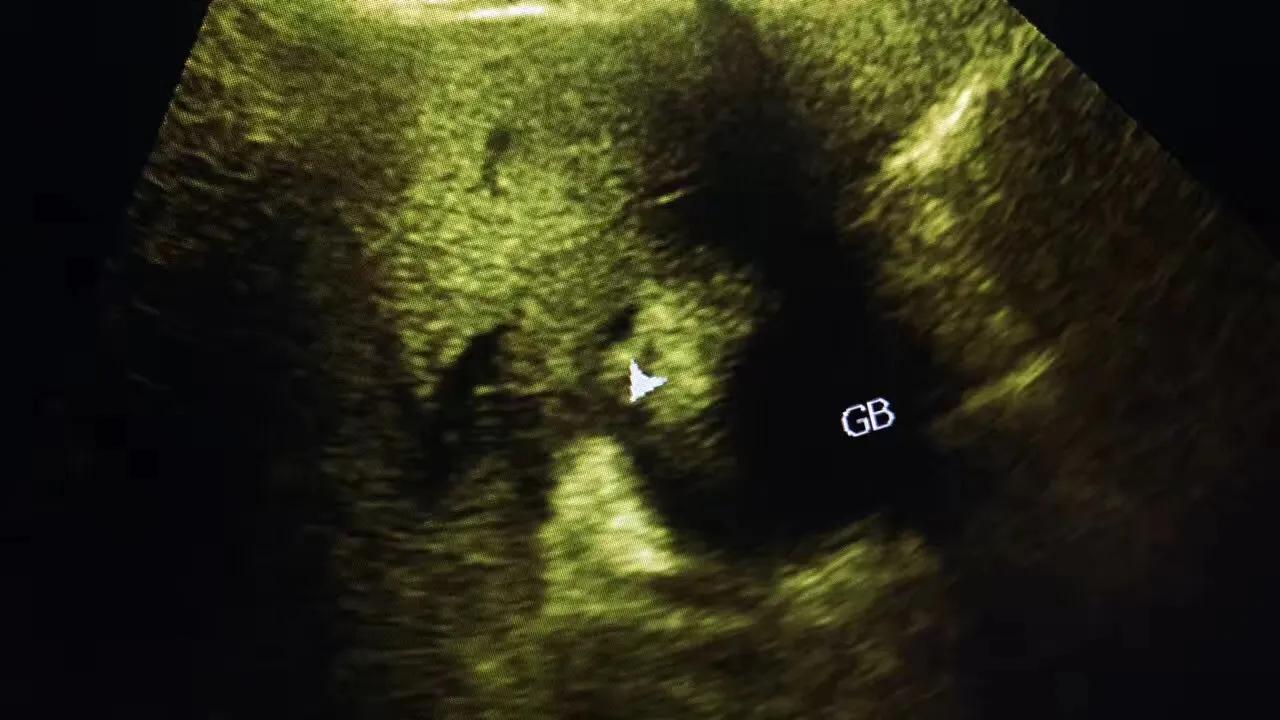

病例2.患者女性,63岁,胆囊颈部结石嵌顿继发急性胆囊炎胆囊穿孔!急诊手术证实胆囊穿孔!